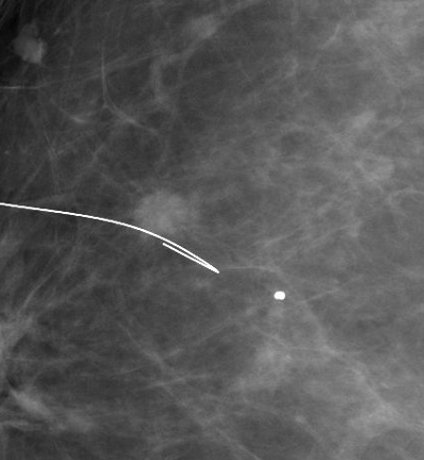

Il s'agit d'une piqûre du sein (de même désagrément qu'une piqûre dans le bras). Quand le radiologue a vérifié par mammographie la position de l'aiguille fine, il enlève l'aiguille, en laissant le repère en place. C'est ce fil que l'on appelle un guide ou harpon .

1 2 3

1 Repérage d'un clip post-biopsies 2 Repérage d'une masse 3 Contrôle per-opératoire de la pièce de tumorectomie (le repère est bien dans la zone d'exérèse)